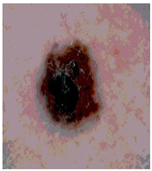

![]() | ![]() | ![]() | ![]() |

| Img1 | --- Pixel Intensity (0–255) ---> | ||

| Img2 | --- Pixel Intensity (0–255) ---> | ||

| Img3 | --- Pixel Intensity (0–255) ---> | ||

| Img4 | --- Pixel Intensity (0–255) ---> | ||

| Img5 | --- Pixel Intensity (0–255) ---> | ||

| Img6 | --- Pixel Intensity (0–255) ---> | ||

| Img7 | --- Pixel Intensity (0–255) ---> | ||

| Img8 | --- Pixel Intensity (0–255) ---> | ||

| Img9 | --- Pixel Intensity (0–255) ---> | ||

| Img10 | --- Pixel Intensity (0–255) ---> | ||